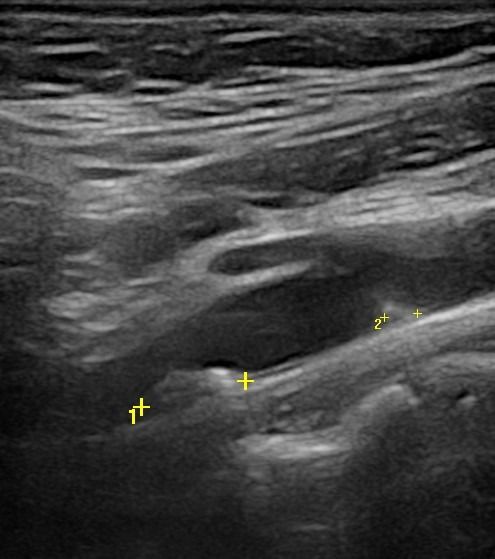

- Αθηρωματικές Πλάκες: Η ποιότητα και η σταθερότητα των αθηρωματικών πλακών είναι κρίσιμη για την πρόβλεψη του κινδύνου αποκόλλησης και εμφάνισης εγκεφαλικού επεισοδίου. Η εξέταση εντοπίζει αν οι πλάκες είναι μαλακές και ασταθείς.

- Ελαστογραφική Μελέτη: Εξετάζει την ελαστικότητα της αθηρωματικής πλάκας, διαπιστώνοντας αν είναι μαλακή και ασταθής, γεγονός που μπορεί να επηρεάσει την πιθανότητα αποκόλλησης και να έχει σαν επακόλουθο ισχαιμικό εγκεφαλικό επεισόδιο.